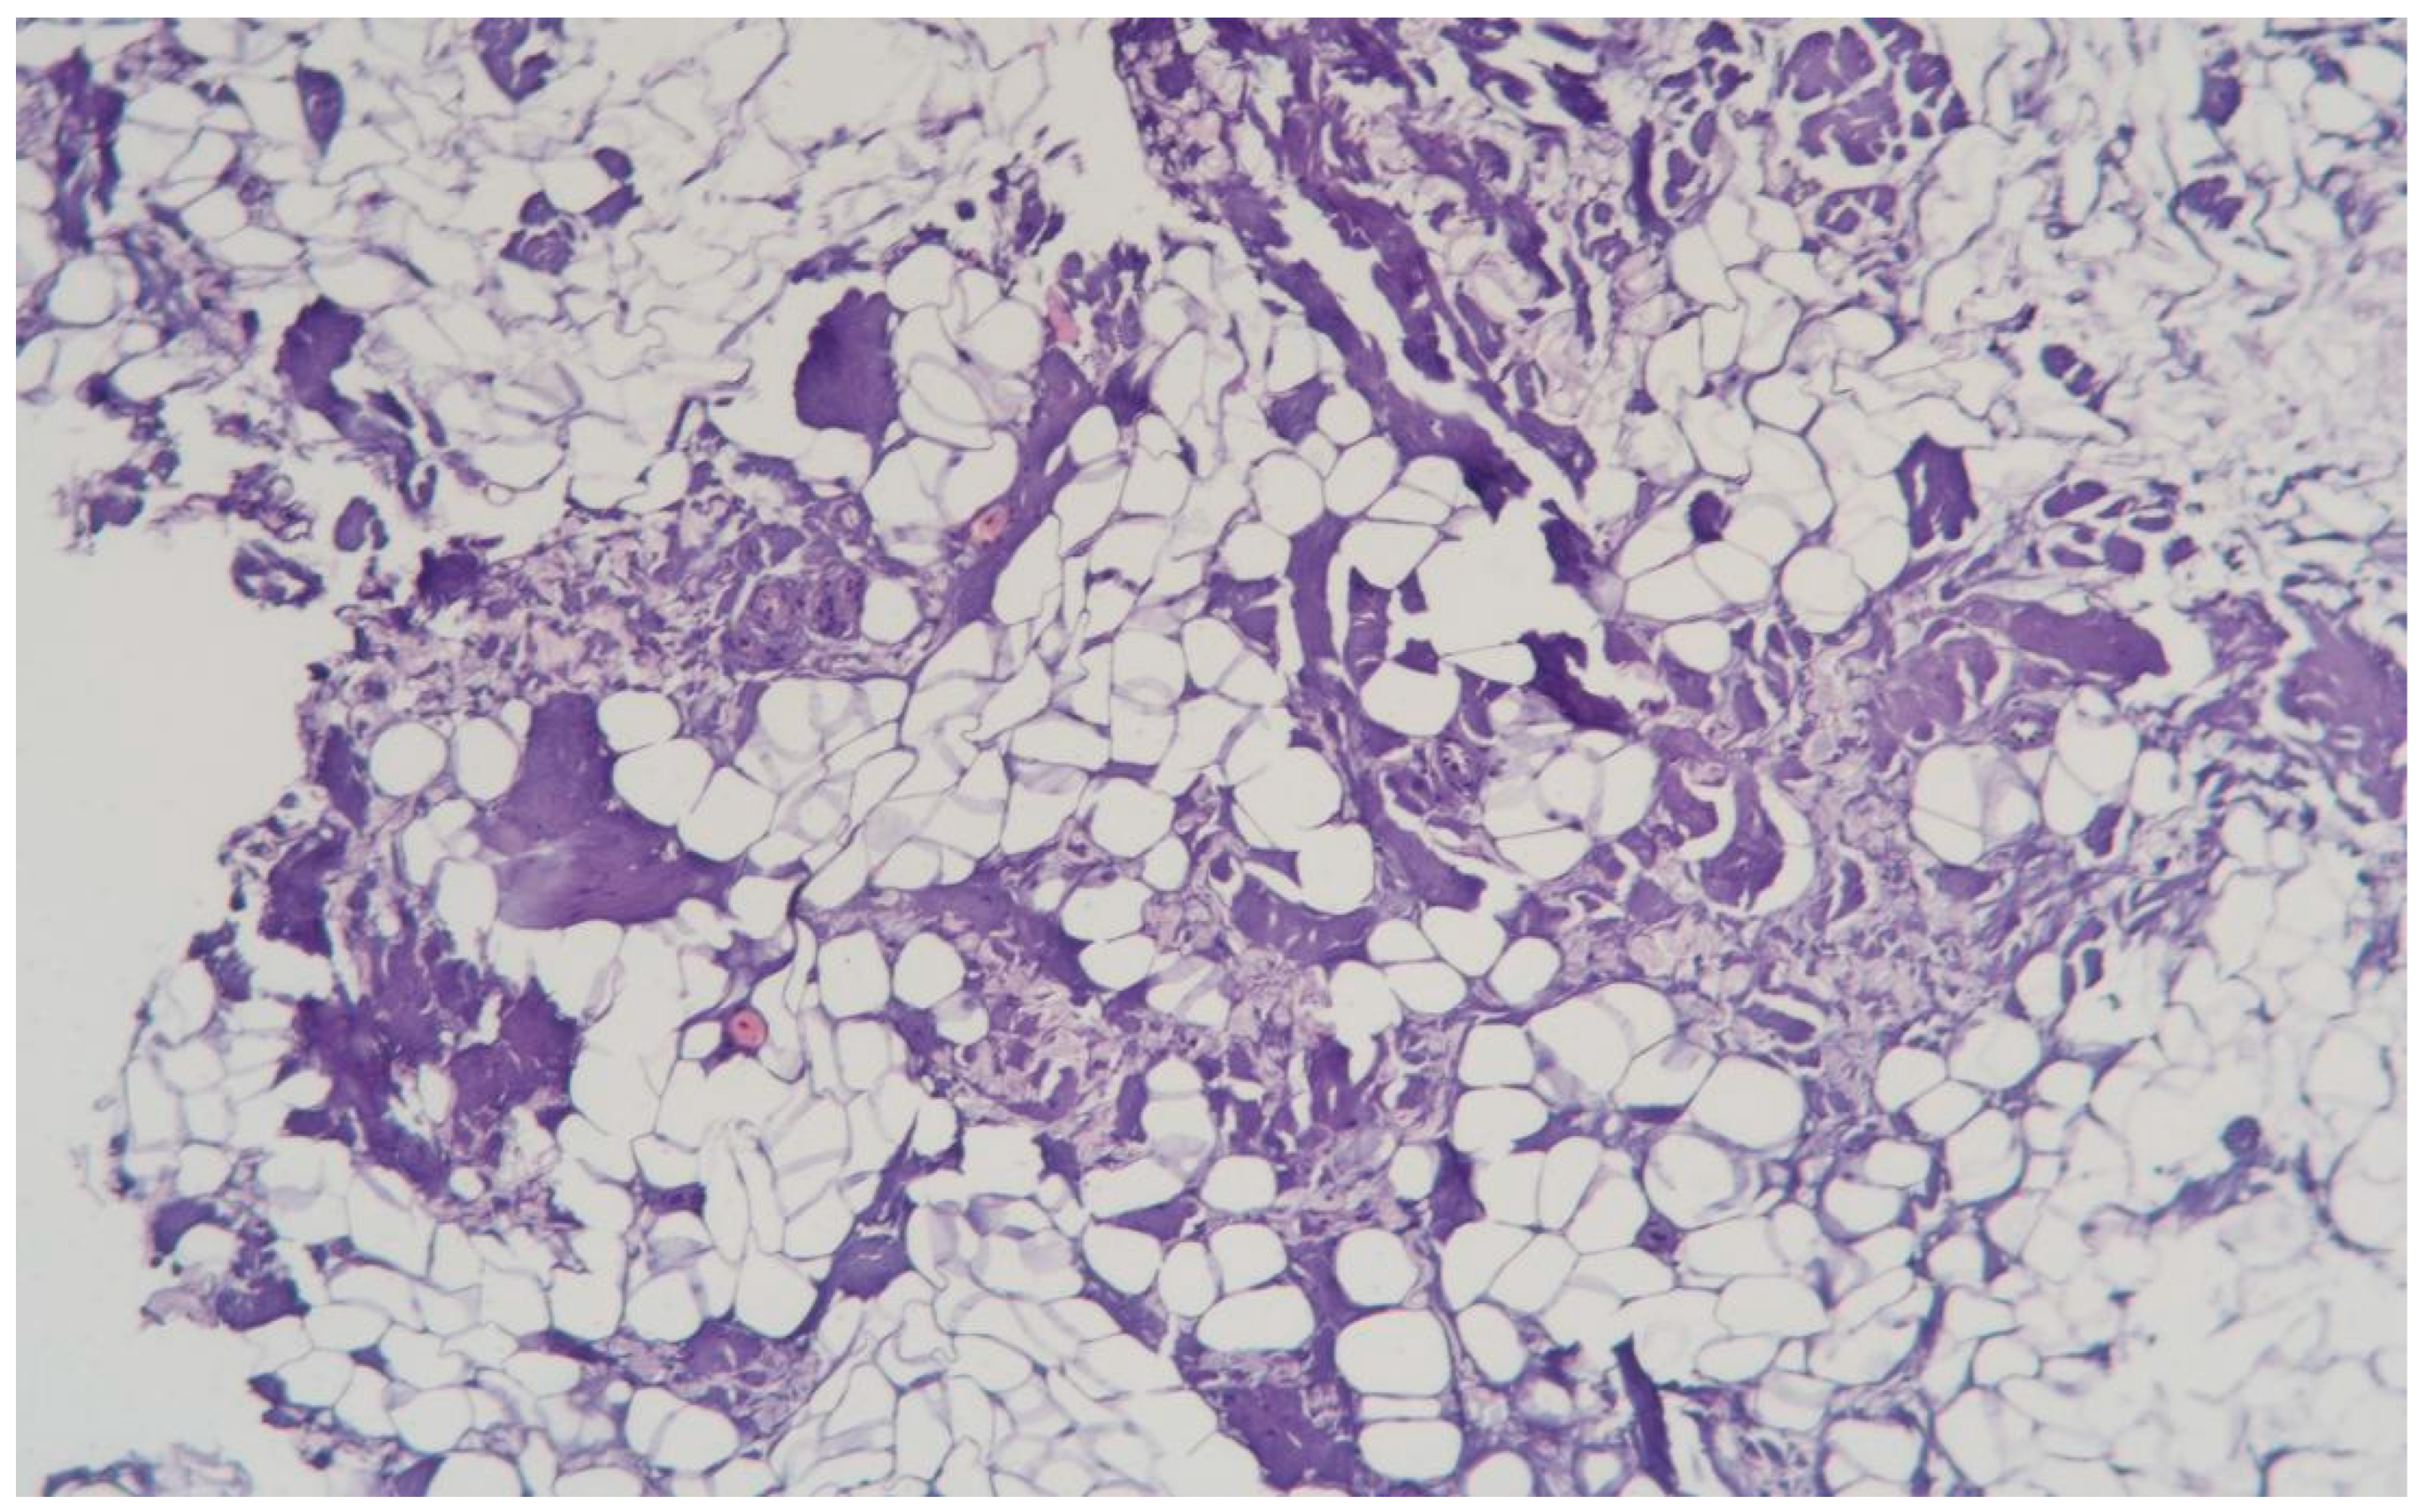

3.1.10. Clinical Case 10: Adipose Tissue Dissection Area, 25 W (See Figure 11)

Description: Coagulative necrosis mainly spread along the septa. The adipose tissue was preserved, but extensive hemorrhages were observed in the interlobular spaces. Inflammatory changes were absent. The vessels were dilated and markedly congested, with thickened and edematous walls.

Figure 11.

Changes in subcutaneous adipose tissue following exposure to the thulium laser at 25 W. H&E staining, 10× objective magnification.